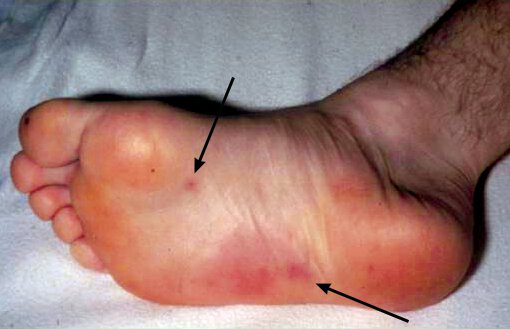

Diagnose: Non tender, multiple lesions.

Janeway lesions are macular, erythematous, nontender microabscesses in the dermis of the palms and soles caused by septic emboli that are considered pathognomonic for IE.